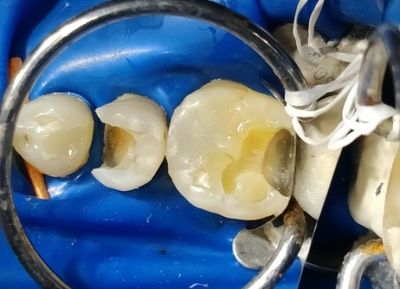

Isolation: we always do root canal under rubber dam isolation. The safest and healthy practice.

Removing pulp– an opening is made and the diseased tooth pulp is removed.

Filling the root canal space – the roots that have been opened (to get rid of the disease pulp) are filled with gutta-percha material and sealed off with composite.